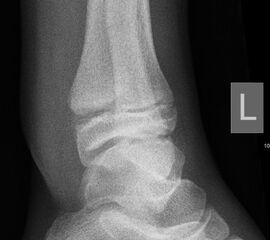

Fugengelenkfrakturen treten typischerweise vor dem 10. Lebensjahr auf, in einer Phase, in welcher die Wachstumsfugen noch weit offen sind. Dieser Frakturtyp betrifft fast ausschließlich den medialen Malleolus. Laterale Frakturen sind extrem selten, teilweise kommt es zu lateralen Bandverletzungen oder Fugenschaftfrakturen der distalen Fibula. Die Frakturlinie verläuft in einer Verlängerungslinie von der medialen Taluskante nach proximal. Häufig stellen sich Verletzungen des Innenknöchels im Röntgenbild schlechter dar, insbesondere wenn die Aufnahmen verdreht sind oder die Ebene der Fraktur bei geringer Dislokation verkippt zur Röntgenebene liegt. Besteht klinisch der geringste Hinweis auf eine Verletzung des Innenknöchels, muss aufgrund der Tragweite der Verletzung durch entsprechende Aufnahmen gegebenenfalls auch Schnittbildverfahren die Verletzung sicher diagnostiziert oder ausgeschlossen werden (Abb. 15).

„Kadiläsion“- Mediale Malleolarfraktur

Bei kindlichen Verletzungen des medialen Malleolus handelt es sich nach L. v. Laer um eine sogenannte Kadiläsion, d.h. eine Verletzung mit hohem Risiko eines schlechten Behandlungsergebnisses bei nicht korrekter Behandlung. Selbst bei optimaler Therapie ist das Risiko für spätere Wachstumsstörungen hoch, sodass diese Verletzungen nicht selten ein juristisches Nachspiel haben. Durch die Verletzung der wachstumsaktiven Zone kann es zu einem vorzeitigen Verschluss der Wachstumsfuge kommen, mit entsprechendem Fehlwachstum. Das Risiko eines vorzeitigen Verschlusses der Wachstumsfuge korreliert mit dem Ausmaß der Schädigung der wachstumsaktiven Zone. Ab dem 13. Lebensjahr wird das Risiko bei reduzierter Wachstumsaktivität zunehmend geringer.

Fugengelenkfrakturen können die Wachstumsfuge durchkreuzen (Abbildung 16a), ohne oder nur mit minimaler Beteiligung der Fuge sehr weit medial liegen (Abbildung 16b) oder durch die Fuge auslaufen (Abbildung 16c). Relevant für die Wachstumsprognose ist weniger die Form der Fraktur, sondern das Alter des Patienten zum Zeitpunkt des Traumas sowie das Ausmaß der Schädigung der Wachstumsfuge, wobei eine Korrelation mit dem Ausmaß der Dislokation besteht.